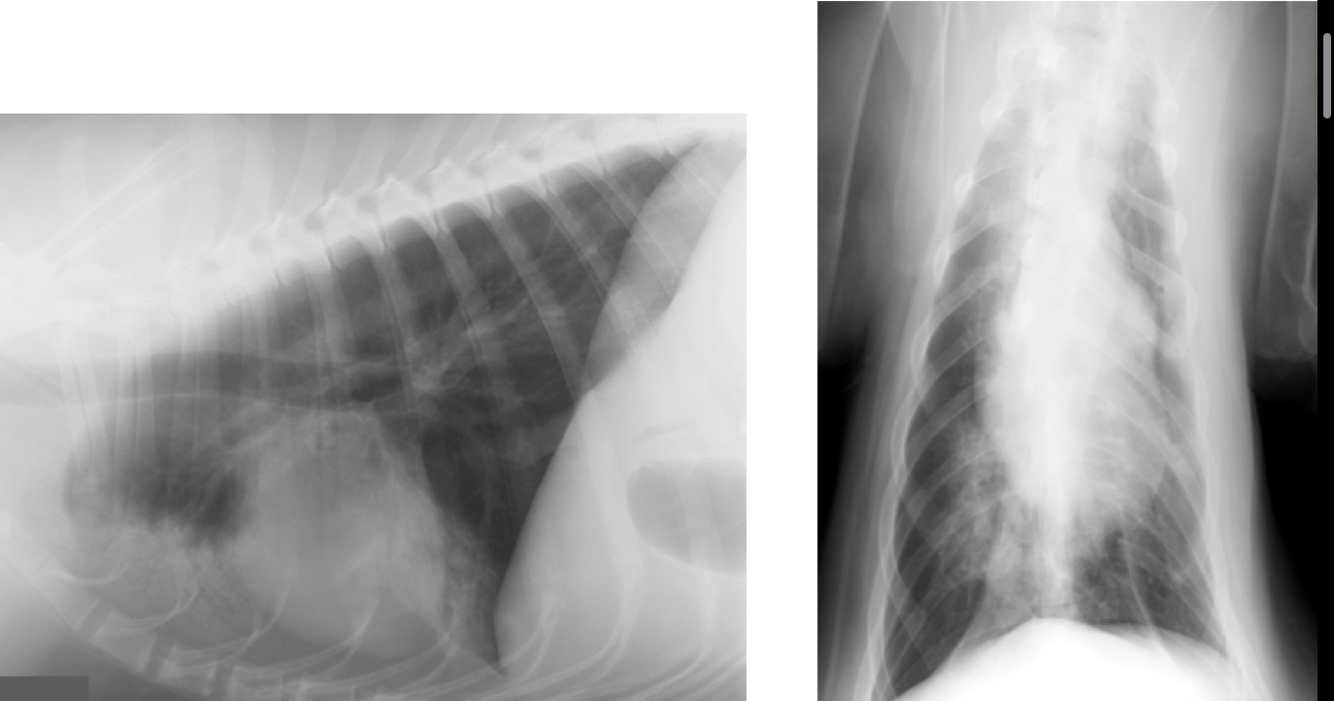

classify distribution

A

Diffuse

Q

Focal

multifocal